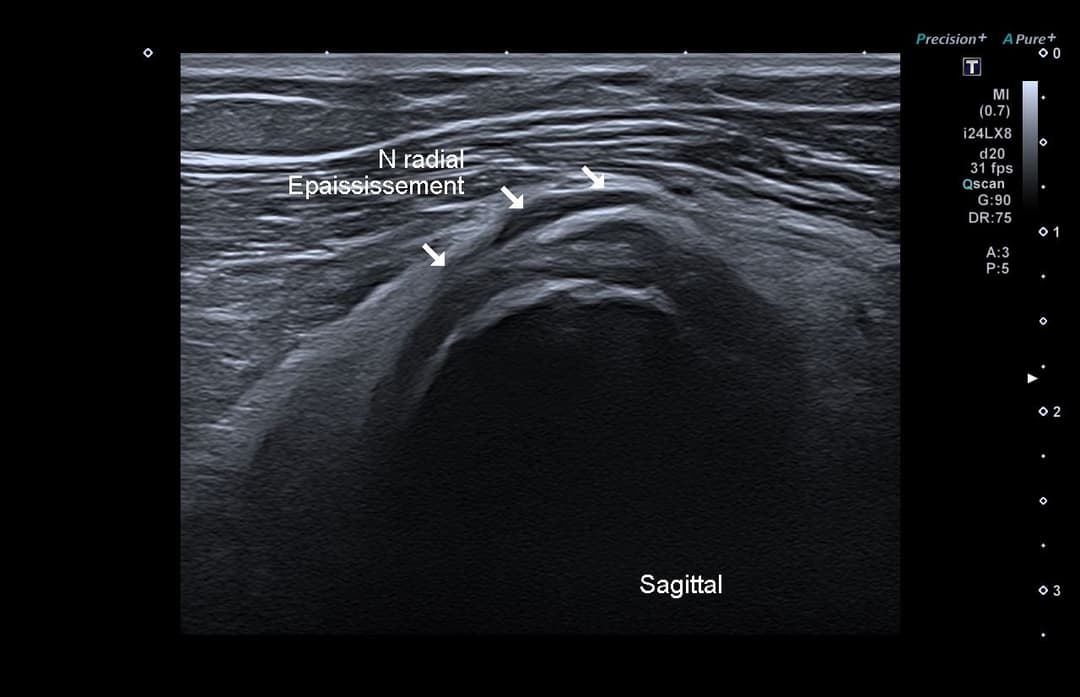

Échographie

Compression du nerf radial qui présente une perte de son parallélisme et un épaississement hypoéchogène à son passage en regard de la structure.